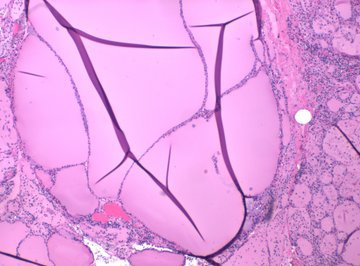

Дерматолог Ирина Баранова перечислила самые частые вопросы про здоровье щитовидки. Она управляет нашим метаболизмом, ростом, развитием, а также влияет на работу всех систем организма.